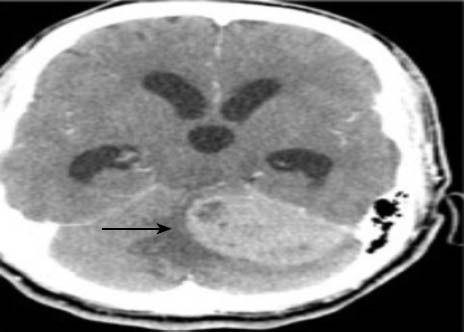

Figure 1.

Brain CT (axial view) demonstrating a left cerebellopontine mass with distention of the third ventricle, the frontal and the temporal horns of the lateral ventricles.

Later that same evening, the patient returned to the emergency room with a new chief complaint of dizziness and difficulty ambulating. His vital signs were as follows: blood pressure 144/88 mmHg, pulse 42 beats per minute, oral temperature 98.1 degrees Fahrenheit, respiratory rate 16 breaths per minute, and pulse oximetry 99 percent on room air. The patient showed nauseous and ill appearance. Repeat neurological exam demonstrated impressive dysmetria, a positive Romberg sign, and most significantly, a wide, unsteady, slowed gait. ED non-contrast computed tomography of the brain demonstrated a 5.1 cm left cerebellopontine angle mass with significant obstructive hydrocephalus and bilateral cerebellar tonsillar herniation (Figures 1–3). Neurosurgery was emergently consulted and treatment was recommended with IV dexamethasone and furosemide. Repeat vital signs showed a blood pressure of 180/100 mmHg, a pulse 39 beats per minute and a respiratory rate of 10 shallow breaths per minute. Due to the patient's rapid clinical decompensation, the patient was taken for an emergent ventriculostomy and left posterior fossa craniectomy for subtotal resection of the mass. Immediate frozen section revealed a grade IV medulloblastoma. During the hospital course, the patient was given craniospinal irradiation with chemotherapy, and was eventually discharged from the hospital to an assisted living facility after an uneventful 15-day course with the aid of social work.